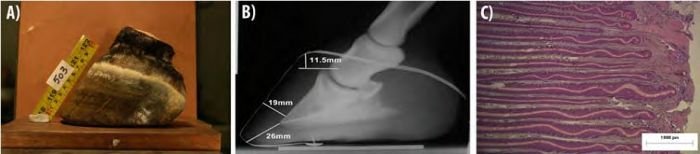

Kopyta koní, kteří žili na tvrdém povrchu, byla krátká, pevná, se silnou stěnou i chodidlem a na pohled líbivá – lze říci ideální. Ve skutečnosti pevná nejen vypadala, chovala se tak trochu jako tvrdá, nepoddajná krabice. Měla strmější patky (45°±2°) i boční stěny (84° vnější a 85° vnitřní), přední stěnu silnou 19-21 mm a chodidlo až 18 mm. Takové kopyto díky své pevnosti skutečně dokáže odolávat četným nárazům o tvrdý povrch a je dostatečně necitlivé, aby se kůň po tomto prostředí mohl bezbolestně pohybovat na dlouhých vzdálenostech, což potřebuje k přežití.

Tým dr. Hampsona provedl zajímavý experiment, kdy kopyta zatěžoval a zkoumal, které části se přitom dotknou země (viz obrázek vpravo): Ani při síle odpovídající cvalu se střel vůbec nedotkl země a kopyto neslo veškerou váhu jen na svém nosném okraji, tvořeném především mozolem okraje chodidla a patkami. Vzhledem k výše uvedeným nálezům (obrovské procento zkostnatělých chrupavek a ztráta špice kopytní kosti) je evidentní, že tlumící funkce těchto „ideálních" kopyt, ač s nejvyvinutějšími měkkými částmi, selhala. Ustoupila totiž jeho ochranné funkci: rohové pouzdro se doslova opancéřovalo, aby si ho koně při svých denních pochůzkách neobrousili do živého. Na druhou stranu díky tomuto silnému „obalu" mohli koně pravidelně ujít i s tak závažnými patologiemi velké vzdálenosti za vodou a potravou.